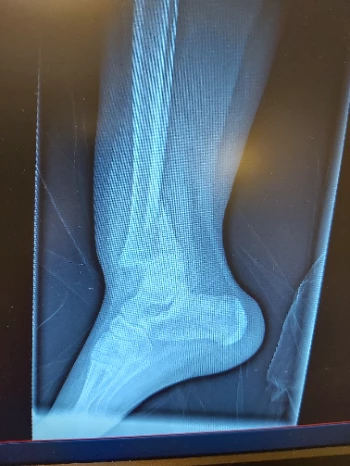

Elleboog: 2 operaties, Openpolsbreuk ook 2 operaties, scheenbeen, kuitbeen, groeischijf + 3x knieschijf knie is geopereerd, dijbeen op 3 plaatsen gebroken, rug ineengezak voor 32%

Nu zit er een ijzerenstaaf van zijn heup tot zijn knie om zijn dijbeen meer steun te geven is te zwak, 15 bouten en 3 ijzerplaten in zijn.enkeltje en een ijzerendraad met 2 bouten rond zijn knieschijf om deze op zijn plaats te houden want door de breuken zat zijn knieschijf 5cm boven waar ze normaal moet zitten. De chirurg heeft ons verwittigd dat als hij nog 1x zijn knie breekt dat ze er dan niets meer aan kunnen doen en zijn been dan zou verliezen. Zijn 1 been is 1cm korter dan het ander waardoor zijn rug en heup scheef begint te groeien. En dit geeft veel pijn en ontstekingen aan zijn rug en heup.

We proberen ook deze zeldzame ziekte meer onder de mensen te krijgen want er zijn maar weinig mensen die deze ziekte kennen. Er zijn zelfs dokters die de ziekte niet kennen zo zeldzaam is het. Het is soms zo erg dat ouders worden beschuldigd van het mishandelen van hun kinderen omdat ze zoveel breuken oplopen. Mijn zoon doet ook mee met een experimenteel onderzoek in Leuven met een nieuw medicijn dat de botten sterker zou moeten maken. Hopelijk gaat dit werken. 10 breuken en 16 operaties is meer dan genoeg geweest en er komt nog 1 operatie voor zijn enkel aan.